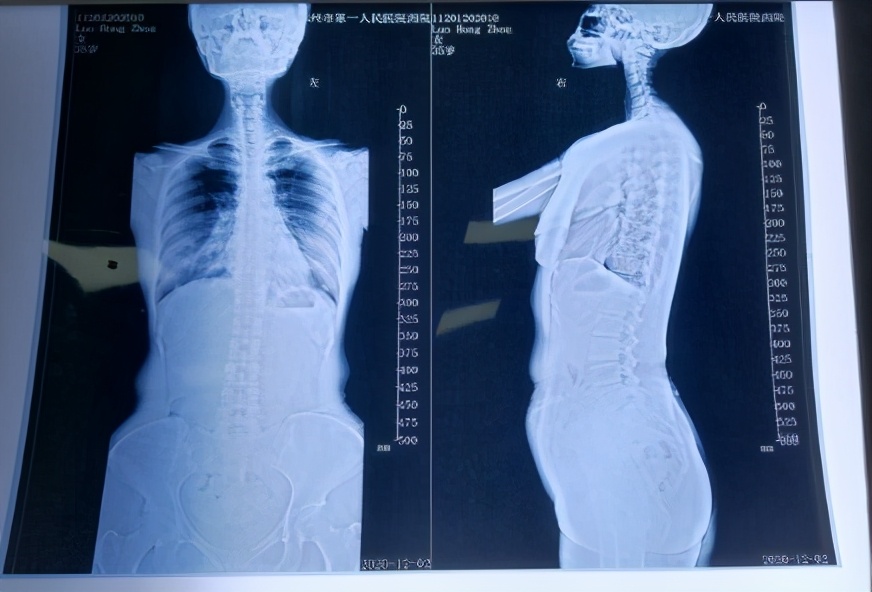

患者影像学检查的结果也证实了这点。

颈椎退变、反弓,右侧C3/4椎间孔狭窄

枕寰间隙缩小,齿状突关节左偏

胸腰段脊柱向左侧弯

骨盆右倾旋转